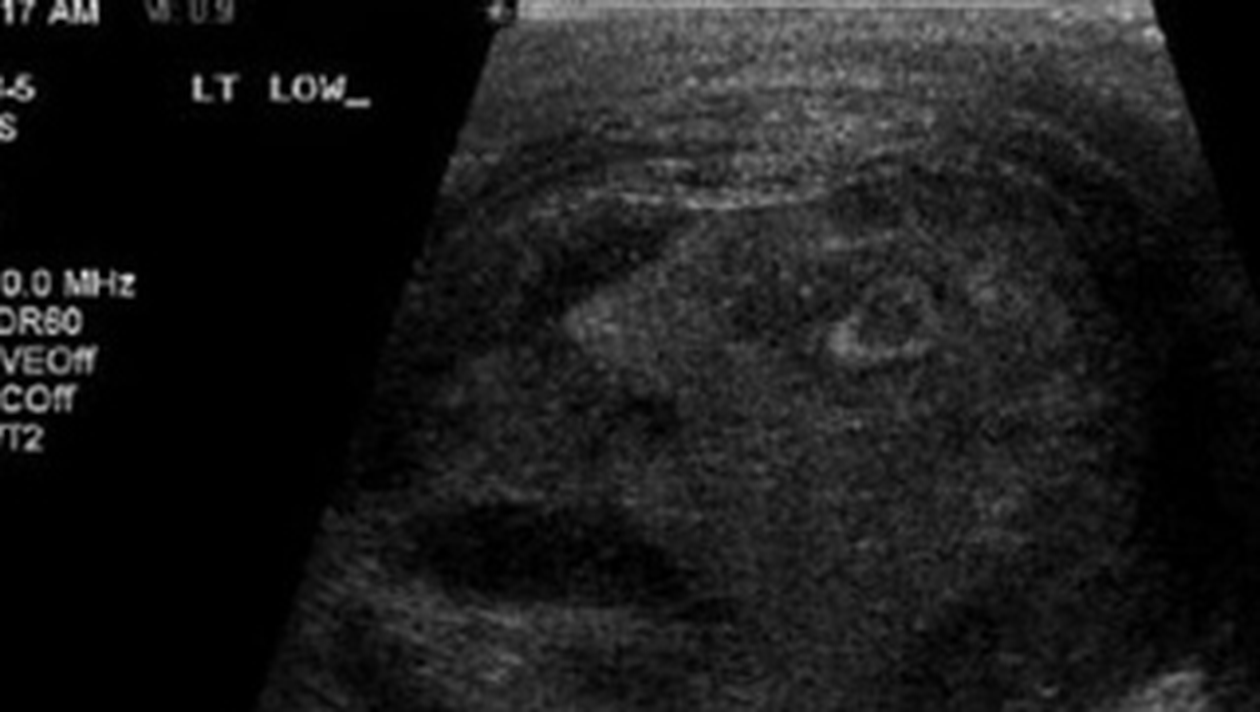

Niste urologi din Canada care-i faceau unui barbat de 45 ani cu o tumoare la testicule un test cu ultrasunete au ramas fara cuvinte cand au vazut in ecografie un chip uman.

In imaginea rezultata in urma analizelor, se poate vedea cu usurinta fata unui om, care pare sa fie chinuit de ceva. „Personalul a fost uimit sa gaseasca conturul unei fete umane, cu privirea indreptata in sus si gura cascata, intr-o expresie care parca arata suferinta severa a acestuia”, au scris medicii in raportul lor. Pentru ca nu au putut accepta sa catalogheze imaginea din ecografie drept o aparitie miraculoasa, doctorii au publicat-o intr-un jurnal de specialitate, in speranta ca unii dintre colegii lor de breasla vor gasi o explicatie stiintifica. Pana acum, insa, nimeni nu a putut elucida misterului chipului din ecografie.